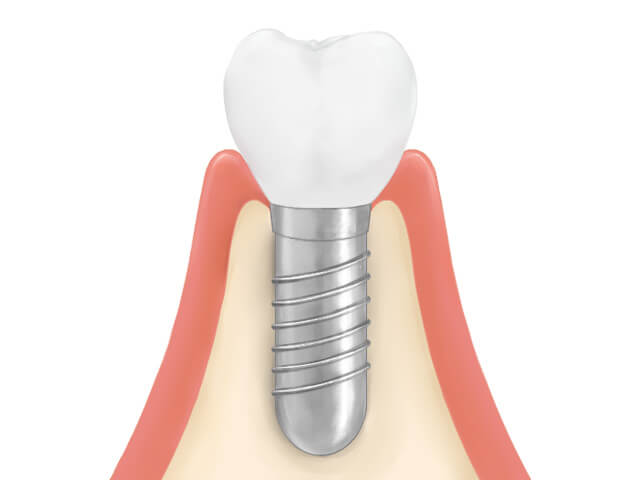

| 治療の説明 | 歯根が破折していた為、診断の結果抜歯が必要となりました。 患者様のご希望で、歯のない部分はインプラントによる治療を行いました。 クラウン(被せ物)は、ジルコニアセラミックスを選択された為、より天然の歯に近い形になりました。 |